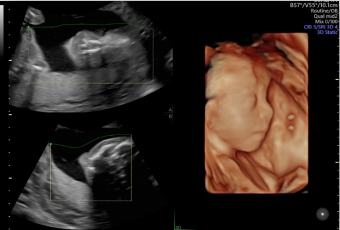

作為超聲領(lǐng)域的領(lǐng)導(dǎo)者,GE醫(yī)療一直走在全球前列。從世界第一臺A型超聲、第一臺實時B型超聲、第一把腔內(nèi)探頭、第一臺3D/4D超聲……一代代的經(jīng)典由此誕生,Voluson超聲也成為了婦產(chǎn)領(lǐng)域的代名詞。

Voluson內(nèi)置自動化技術(shù)幫助醫(yī)生精簡工作流程,減少擊鍵次數(shù);同時提高了測量的一致性和可重復(fù)性,推動檢查效率。

通過自動的放置取樣框綠線并根據(jù)胎兒活動自動調(diào)節(jié),使得容積圖像的獲取更簡單快速。

適用場景:Voluson S6不僅強(qiáng)在婦產(chǎn),它豐富的探頭群和全面的應(yīng)用功能也可以同時兼顧新生兒、兒科、成人全身檢查等,提供一站式的超聲檢查解決方案。